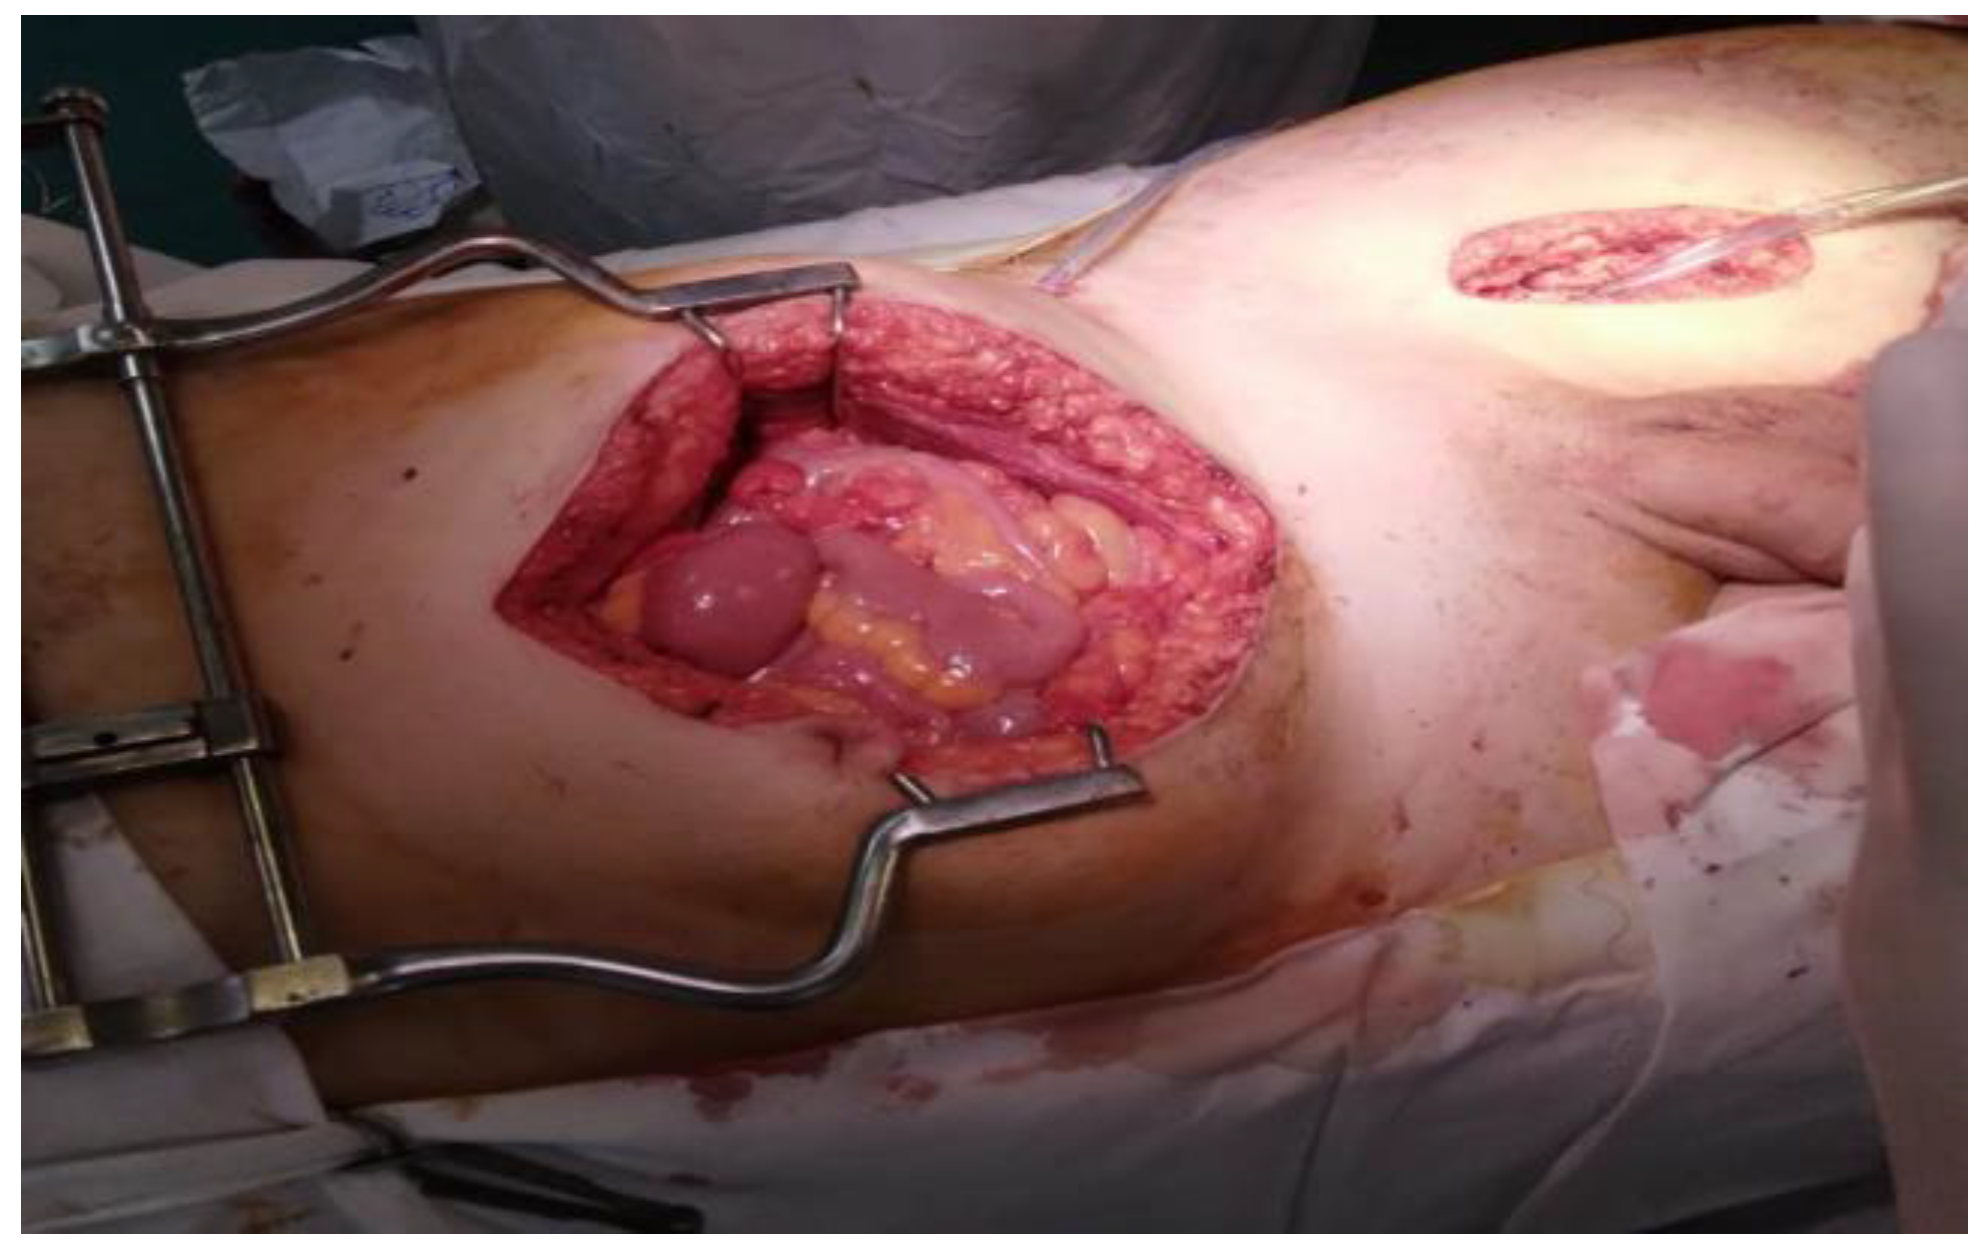

As far as the surgical intervention is concerned, the surgical plan was decided and established after the diagnosis was defined, the specific drug therapy being with albendazole. The objectives of the surgical intervention were the complete and total excision of the cysts (in cases of multiple localization) or, when the ideal cystectomy can be performed: the inactivation of the parasite, the evacuation of the cyst cavity, the elimination of the germinal membrane and the prevention of the intra-operative dissemination of parasites. Complete and total radical cystectomy (in cases with multiple localization) was performed in 4 patients, and pericystectomy and drainage of remaining cavities in 2 patients. All surgical interventions were performed through median laparotomy under orotracheal intubation (Figure 10 and Figure 11).

Figure 10.

Appearance after resection of retroperitoneal hydatid cyst.

Figure 11.

Operative parts: multiple intra-abdominal cysts (intra and retroperitoneal).